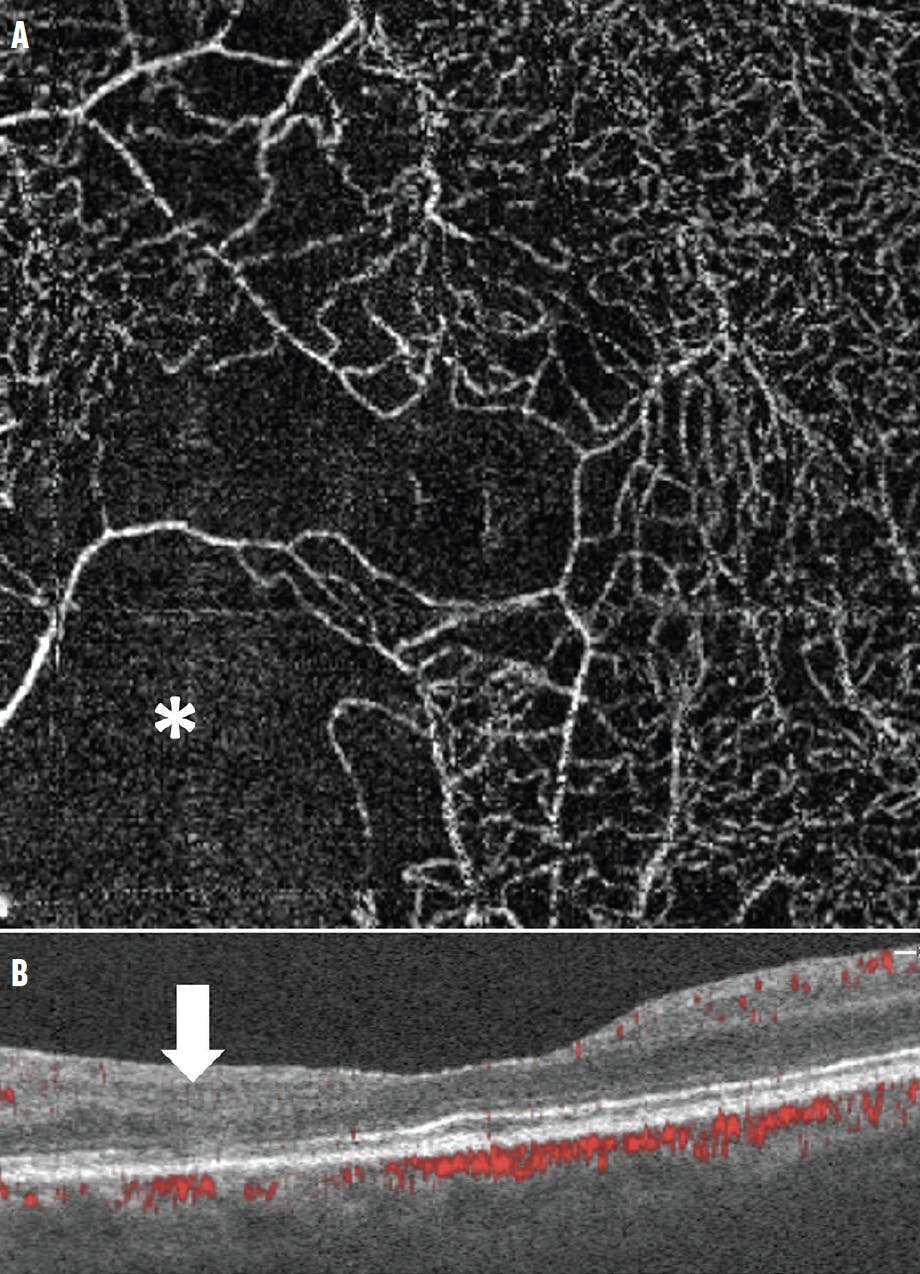

<p>Figure 1. The en face OCTA deep capillary plexus slab of an eye of a 30-year-old woman with type 1 diabetes revealed significant areas of nonperfusion and capillary dropout (A, asterisk). The area of nonperfusion corresponds to a lack of flow seen on the OCT B-scan flow overlay (B, arrow). Note the asymmetry in flow between the temporal and nasal retina. There is also significant thinning of the fovea and temporal retina, including photoreceptor disruption, and disorganization of the retinal inner layers with distortion of the retinal layers on the OCT B-scan.</p>

Figure 1. The en face OCTA deep capillary plexus slab of an eye of a 30-year-old woman with type 1 diabetes revealed significant areas of nonperfusion and capillary dropout (A, asterisk). The area of nonperfusion corresponds to a lack of flow seen on the OCT B-scan flow overlay (B, arrow). Note the asymmetry in flow between the temporal and nasal retina. There is also significant thinning of the fovea and temporal retina, including photoreceptor disruption, and disorganization of the retinal inner layers with distortion of the retinal layers on the OCT B-scan.